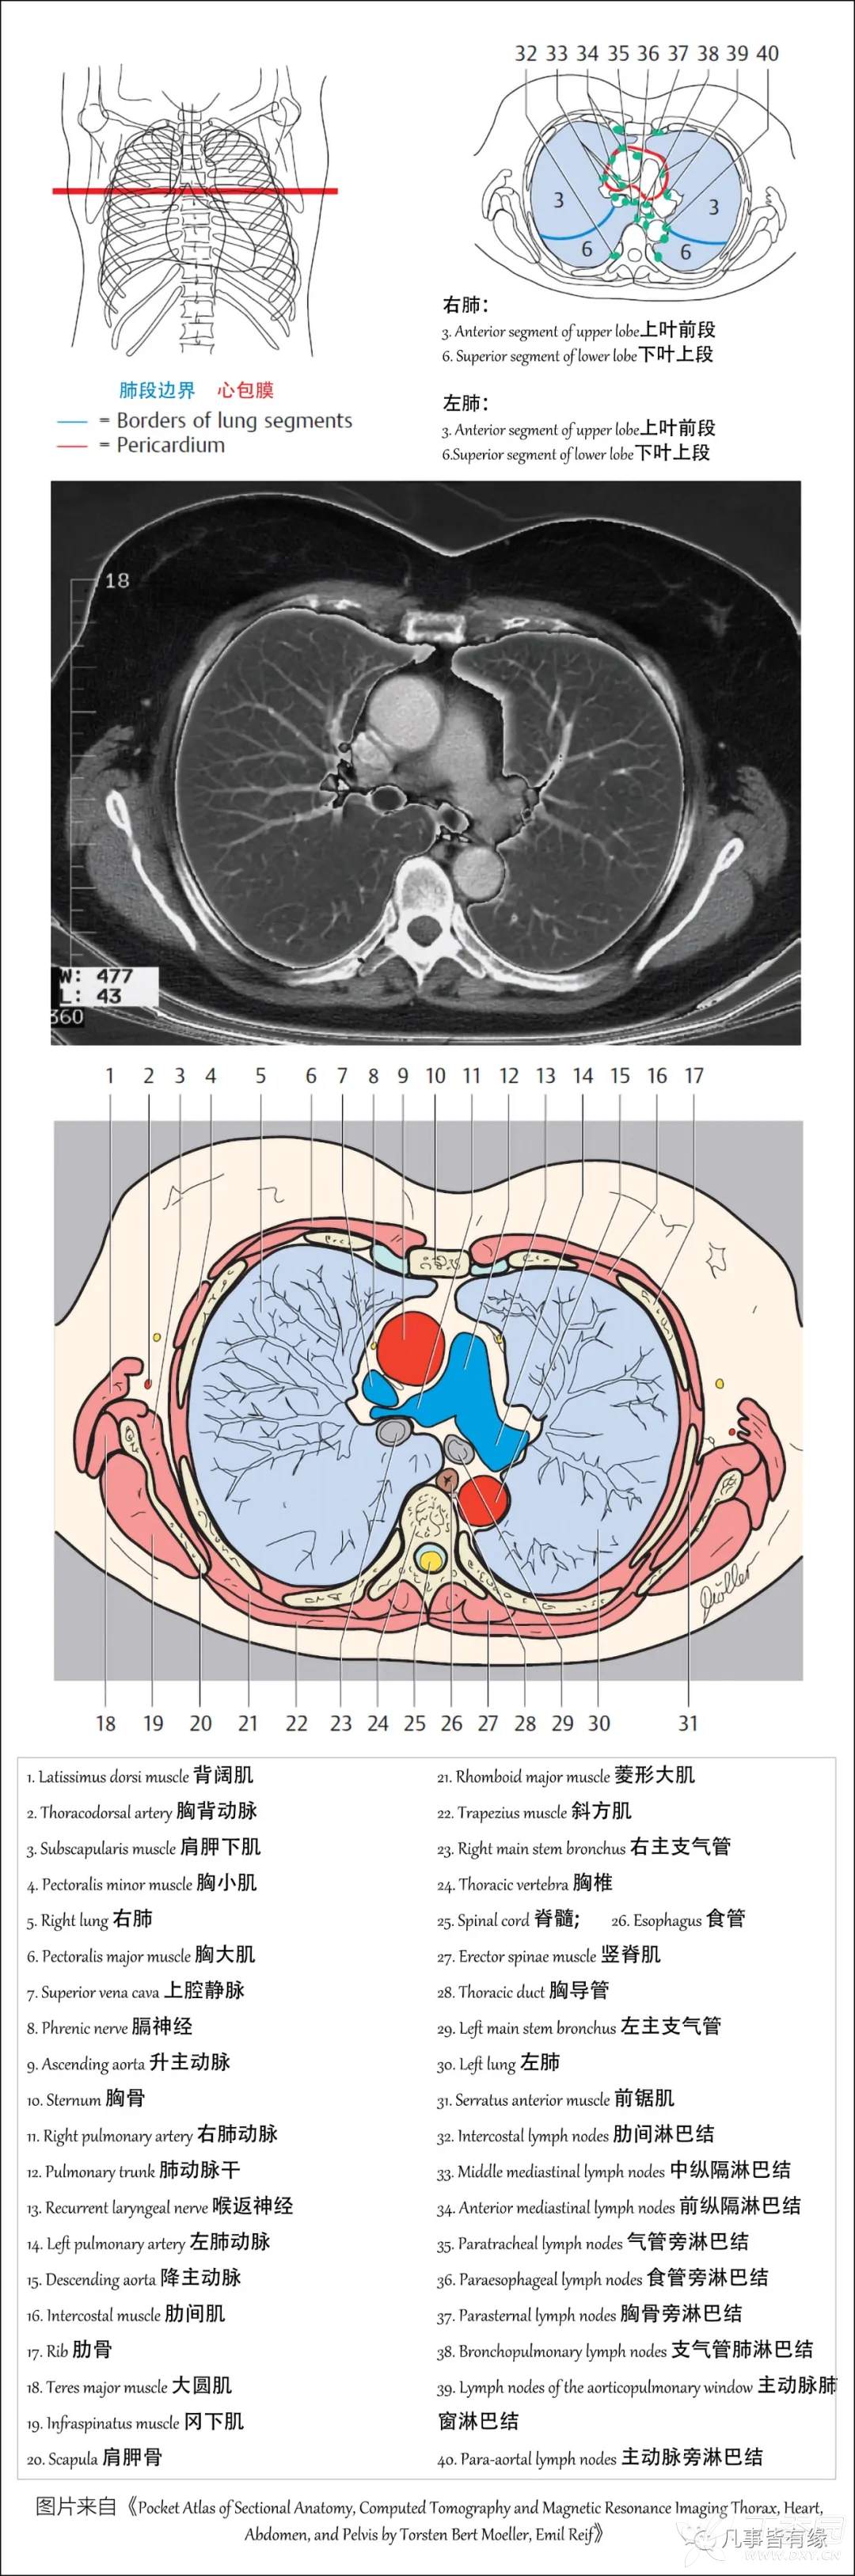

(一)胸部CT轴位断层解剖: